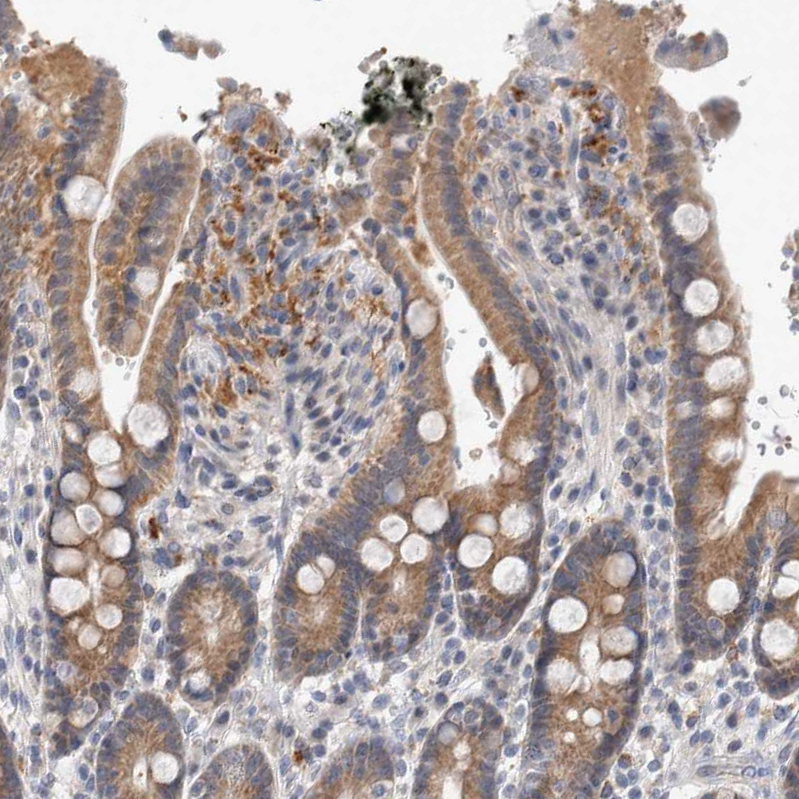

Immunohistochemical staining of human fallopian tube shows moderate cytoplasmic positivity in glandular cells.